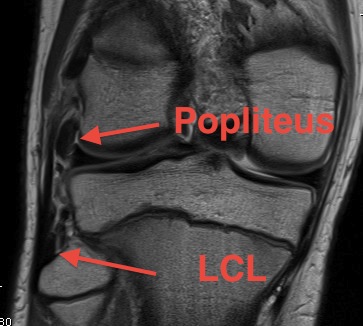

Lateral collateral ligament anatomy

Don't see entire length on single MRI

- use coronal to look for origin from lateral epicondyle above popliteal insertion

- use coronal to look for insertion onto anterolateral fibular head

Normal anatomy

Popliteus anatomy

Don't see entire length on single images

- coronal image to see insertion onto popliteal fossa below LCL

- follow tendon around on coronal images

- watch as becomes musculo-tendinous (can often be torn here)

- muscle inserts onto posteromedial tibia

Normal anatomy